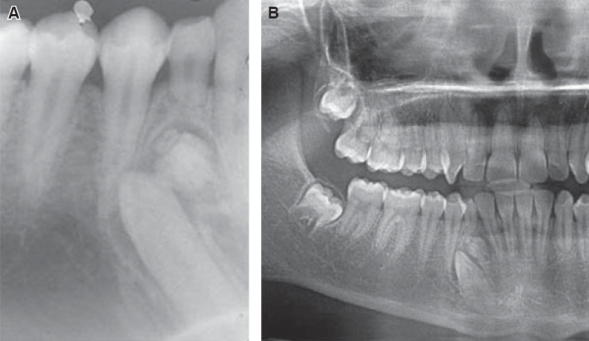

En la literatura se reconocen tres presentaciones clínicas de los odontomas: intraóseos, extraóseos y erupcionados, siendo los intraóseos los más frecuentes.31 La localización más comúnmente reportada es el área incisivo-canina del maxilar superior (67%), seguida por las zonas anteroinferior y posteroinferior de la mandíbula (33%).14,26-28,32 Los OCp se presentan claramente con mayor frecuencia que los odontomas complejos.8 El OCp aparece con mayor frecuencia en la parte anterior del maxilar sobre la corona de un diente(s) no erupcionado(s) o entre las raíces de dientes erupcionados (61%) Figura 1, mientras que el complejo lo hace en la parte posterior de la mandíbula (59%) Figura 2.8,33,34

Figura 2 A) Proyección periapical de odontoma complejo. B) Odontoma complejo en zona de premolares inferiores (ortopantomografía).

Los odontomas compuestos Figura 1 se observan como masas radiopacas de márgenes irregulares que adoptan una configuración similar a dientes, con un borde periférico radiolúcido, mientras los complejos muestran una radiopacidad única.4 Dependiendo del grado de calcificación del odontoma, se pueden identificar tres estadios de desarrollo, en el primero la lesión aparece radiolúcida (debido a la falta de calcificación de los tejidos dentales), en el intermedio se caracteriza por una calcificación parcial y en el final el odontoma aparece radiopaco, rodeado por un halo radiolúcido Figura 2.21